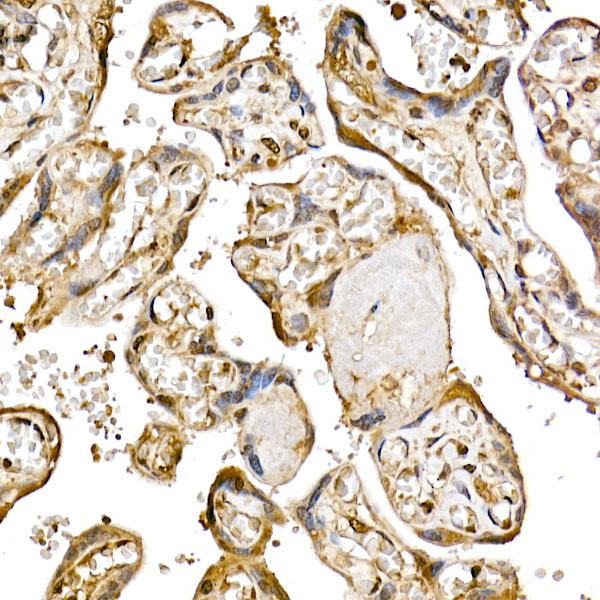

Mammalian target of rapamycin (mTOR) is an atypical serine/threonine kinase that can integrate a variety of extracellular signal stimuli. It is involved in multiple signaling pathways in the body, affecting transcription and protein synthesis. Studies of mTOR found that it has an important connection with processes such as apoptosis, autophagy, and cell growth. For example: 1) mTOR signaling pathway can affect gene transcription and protein synthesis, which plays an important role in cell growth and proliferation. 2) mTOR stability can affect the expression of cytokines in T cells, which is involved in immune suppression. 3) mTOR signaling pathway can affect cell proliferation and protein synthesis, making it a new target for anti-tumor therapy. 4) In addition, mTOR signaling pathway also plays an important regulatory role in diseases such as motor metabolism. mTOR is present in two different complexes, the first being mTOR complex 1 (mTORC1), which consists of mTOR, Raptor, GβL and DEPTOR and is inhibited by rapamycin. The second complex, mTOR complex 2 (mTORC2), consists of mTOR, Rictor, GβL, Sin1, PRR5/Protor-1 and DEPTOR. The function of these two complexes is also different: mTORC1 is responsible for amino acids, oxygen, energy levels, and growth factors, mainly promoting protein synthesis, lipogenesis, energy metabolism, inhibition of autophagy, and lysosome formation. And mTORC2 plays an important role in areas such as muscle Actin cytoskeleton, cell survival, and metabolism.